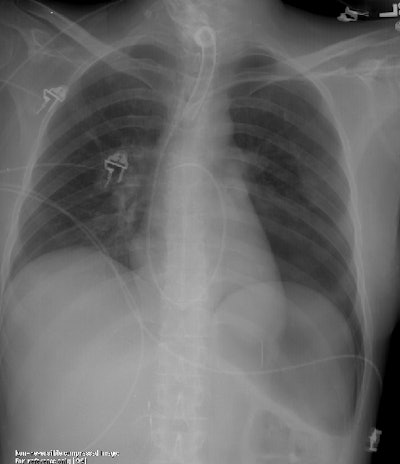

Pneumothorax in a supine patient- the "Deep Sulcus Sign"

The film below was taken on an ICU patient following placement of a Swan-Ganz catheter. The exam demonstrates a large left pneumothorax with a characteristic "deep sulcus sign" in this supine patient.